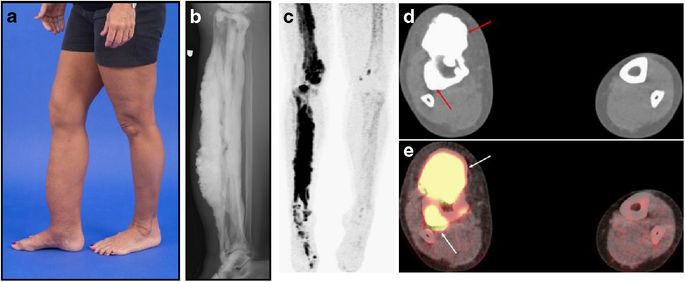

Les lésions osseuses sont faites d’un os normal, mais en excès, et se traduisent en radiographie par une hyperostose de la corticale osseuse s'étendant « en coulée de cire de bougie », souvent le long du corps vertébral d’un os long. Ces condensations peuvent s'associer avec des calcifications ou ossifications des parties molles.

La scintigraphie osseuse, le scanner et l'IRM peuvent être utiles pour le bilan d'extension des lésions et les différencier d’un ostéosarcome paraostéal, des myosites ossifiantes ou des hématomes calcifiés. Les lésions osseuses se situent le plus souvent sur un seul membre, en suivant le trajet d'un sclérotome, mais des lésions multiples diffuses sont possibles.

La mélorhéostose : a = déformation de la jambe droite ; b = Radiographie : condensation et déformation du tibia droit en coulée de cire de bougie ; c = hyperfixation scintigraphique ; d = scanner avec condensation osseuse ; PET-scan = hyperfixation osseuse (Crédit NIH)